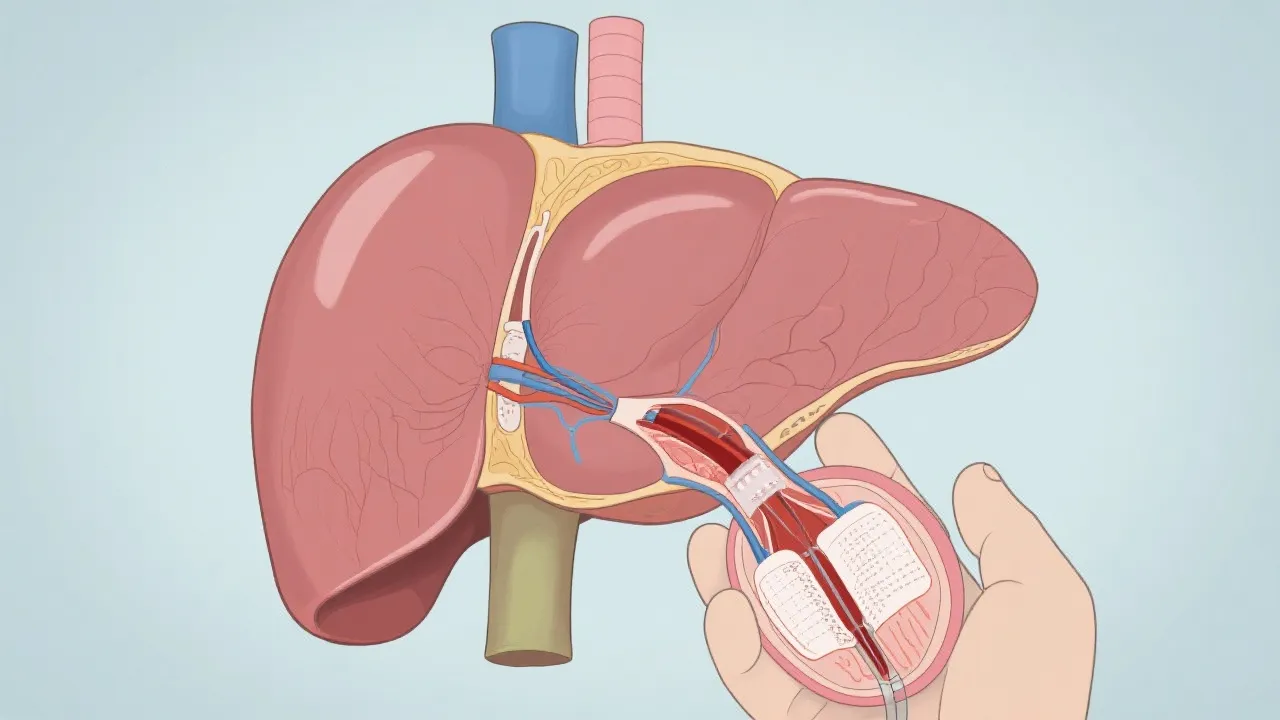

Once a suitable donor is identified, the transplantation procedure entails a complex surgical operation where the diseased liver is meticulously excised and replaced with a healthy liver from a deceased or living donor. The choice of donor can significantly influence the success of the procedure; thus, careful matching based on factors such as blood type, body size, and liver condition is essential. Post-operation, patients require lifelong monitoring and medication to prevent organ rejection and manage their health effectively. Immunosuppressant drugs are critical in this period, as they minimize the risk of the body rejecting the new liver. However, these medications can increase the risk of infections and may lead to other complications, necessitating a delicate and continual balancing act in post-transplant care.

Research into liver transplantation and NASH has yielded promising advancements over the years. With ongoing clinical trials and studies, significant improvements in pre- and post-operative care have led to enhanced survival rates and patient outcomes. Innovative strategies, such as utilizing living donors and developing artificial livers, are being vigorously explored to combat donor organ shortages. Living donor liver transplantation, where a portion of a healthy individual's liver is transplanted, can offer a timely solution for patients awaiting a deceased donor, reducing waiting times and improving prognosis.